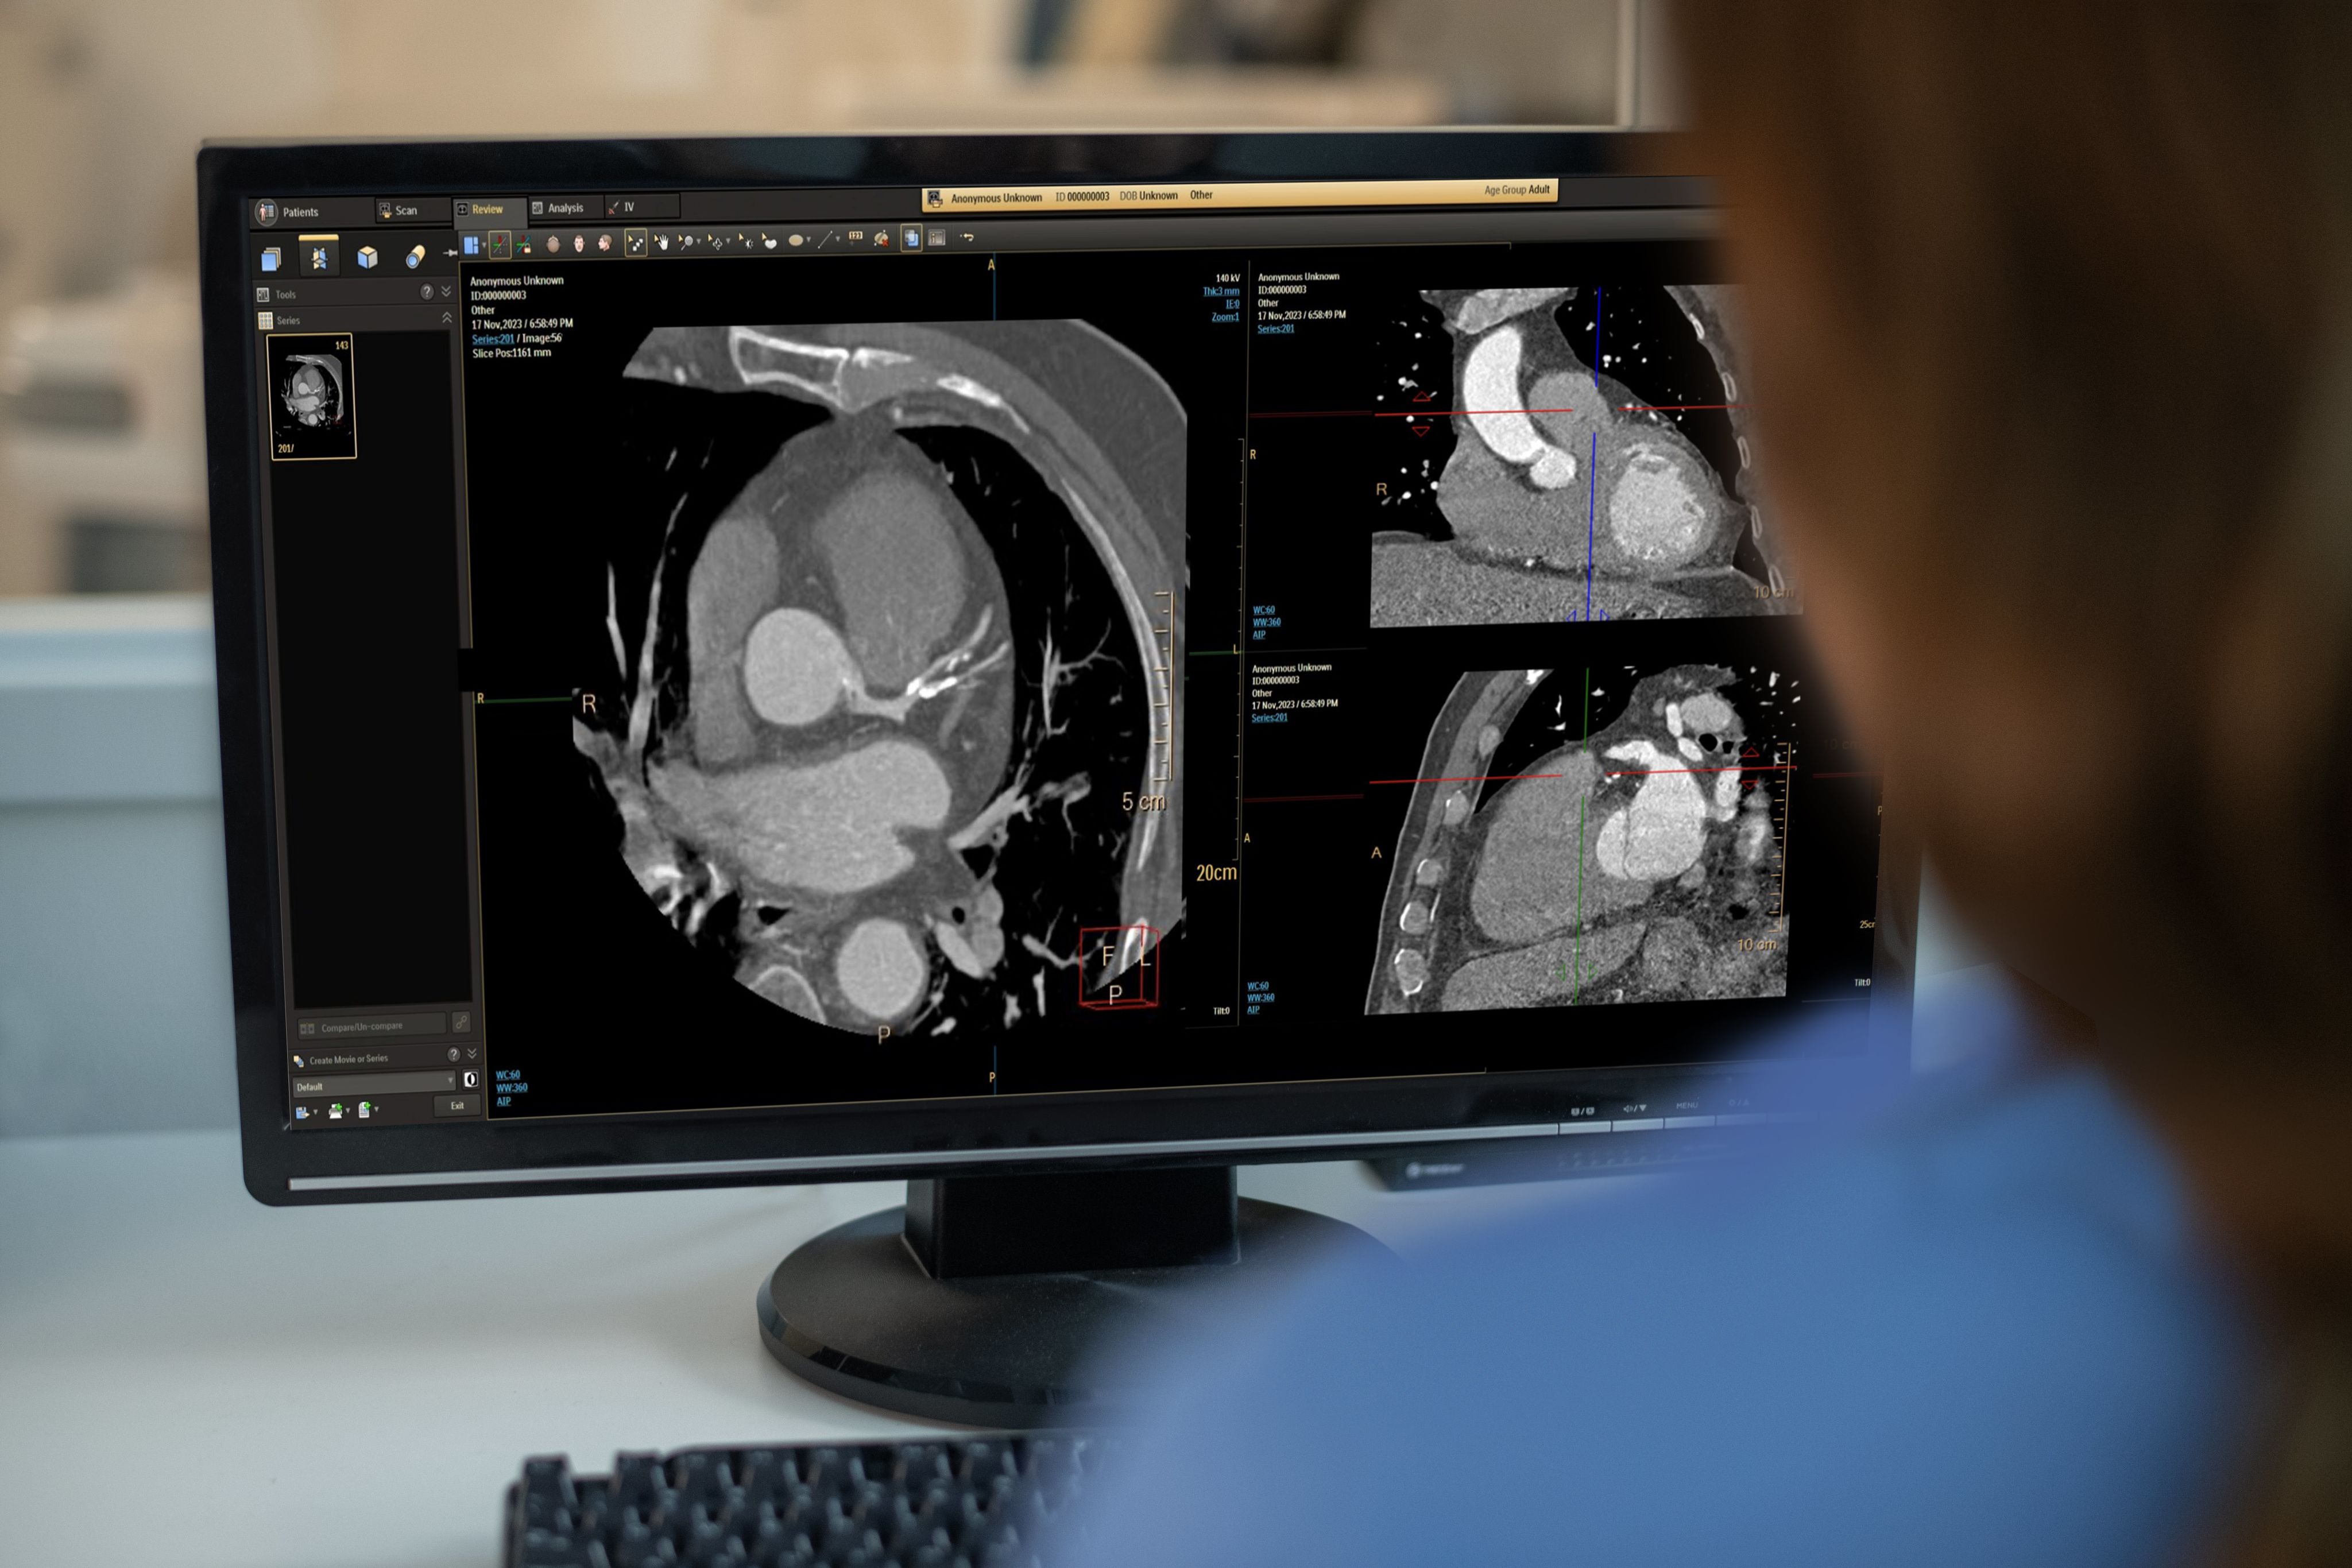

The Philips CT 5300 system features NanoPanel Precise, the industry’s first CT detector built from the ground up specifically for AI-based image reconstruction. This detector leverages the full capabilities of Philips Precise Image AI-reconstruction software to deliver high-quality images at a much lower radiation dose. Combined with Precise Cardiac motion compensation, Precise Image makes the CT 5300 system particularly suitable for high-quality, motion-free cardiac imaging in patients with high heart rates or heart-rate variability.

Precise Cardiac is a reconstruction technique that compensates for cardiac motion to improve visualization of the coronary arteries during CT imaging. This enables clinicians to see what’s happening in the coronary arteries.

Precise Cardiac demonstrates significant improvements in image quality of the coronary arteries, compared with standard cardiac CT reconstructions. Applicable for different types of CT exams (retrospectively gated helical exams and prospectively gated axial exams), Precise Cardiac employs efficient filtering techniques in a predefined region around the targeted cardiac phase to identify relevant objects and dynamically track their motion behaviour in the localized portion of the cardiac cycle. Motion-corrected images are generated by taking into account the displacement of structures and performing the relevant corrections as part of the reconstruction process.

Smart automation in this advanced CT system

Precise Cardiac is built into the CT workflow, avoiding the need for any manual intervention by the person doing the scanning, the need for data transfer or the need for additional workstations. It improves diagnostic confidence in challenging patients with high or irregular heart rates and can help a clinician salvage some coronary segments previously deemed nondiagnostic using standard cardiac reconstructions, thus increasing diagnostic confidence in coronary CTA exams. Coronary motion correction can potentially reduce the need for a repeat scan.

AI-enabled cardiac scanning at every step Cardiac imaging is advancing. From scan preparation through reconstruction, the powerful Philips AI-enabled innovations in cardiac imaging matter. Tools like Precise Image AI reconstruction and Precise Cardiac for motion-corrected images help deliver precision in dose, speed and image quality.